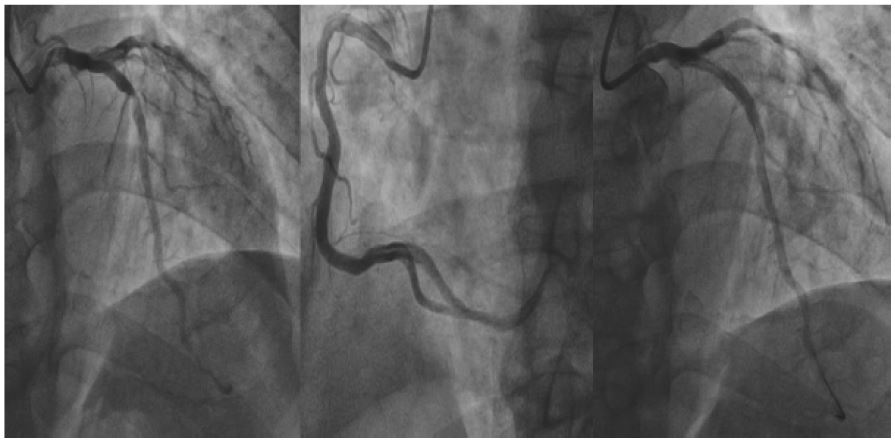

Figure 2: Findings of the patient at the second coronary angiography.

Cardiac enzymes: creatine kinase isoenzyme 4 ng/mL, myoglobin 220 ng/mL, troponin I 0.06 ng/mL. There were no obvious abnormalities in liver and kidney function, electrolytes and blood coagulation test. Urgent electrocardiogram showed sinus rhythm, Q wave formation in leads II, III, and aVF, and ST segment elevation of about 0.3 mV. The diagnosis was as follows: 1. coronary heart disease, acute ST-segment elevation myocardial infarction (inferior wall), cardiac function class I (Killip class) 2. Hypertension 3. Syphilis. Aspirin 0.3 g and ticagrelor 180 mg were given to the patient in bed. Emergency coronary angiography showed that there was no significant stenosis in the proximal segment of LM (left main artery), no significant stenosis in the proximal segment of LAD (Left Anterior Descending artery), thrombus stenosis in the middle segment of LAD was about 99%, and no significant stenosis in the distal segment. No obvious abnormality was found in LCX (left circumflex artery). The proximal segment stenosis of OM (Obtuse Marginal branch) was about 80%. RCA (right coronary artery) was thick with nonsmooth intima in the proximal and middle segments, and no significant stenosis was seen throughout (Figure 1). As the culprit vessel could not be located and the possibility of recanalization of RCA could not be excluded, urokinase 100000u and heparin 1000u were injected into the left and right coronary arteries respectively, and the operation was completed and the patient returned to the intensive care unit for hospitalization. The patient had no discomfort such as chest pain or chest tightness during and after the operation. Electrocardiogram was reexamined daily during admission, and pathological Q waves in leads II, III, and aVF were deepened, and ST segment gradually fell back to baseline level on the third day. Cardiac perfusion on the 5th day after admission showed acute ischemic cardiomyopathy changes in the inferior septal wall of the apical segment and the inferior wall of the left ventricle, and the inferior wall of the basal segment of the left ventricle, suggesting poor healing locally. Based on the results, the culprit vessel of this myocardial infarction was LAD. Reexamination of angiography on the 10th day after admission showed that the thrombus disappeared in the middle segment of LAD, the localized lesion was about 90%, and there was no significant change in LCX and RCA compared with before (Figure 2). Then a stent was implanted into the middle segment of LAD. The patient was discharged on the 12th day after admission.